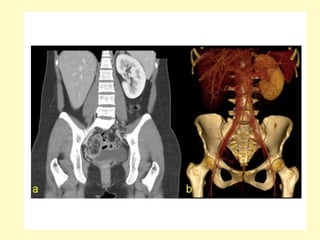

Horseshoe kidney with anteriorly oriented renal pelvis, axial contrast-

enhanced MDCT image (a) shows a horseshoe, the renal isthmus is

found anterior to the great retroperitoneal vessels, corresponding

volume rendering (b) better show the inferior renal isthmus, the

normal renal arteries, and the anterior location of the renal pelvises

I = isthmus, IMA (arrow)